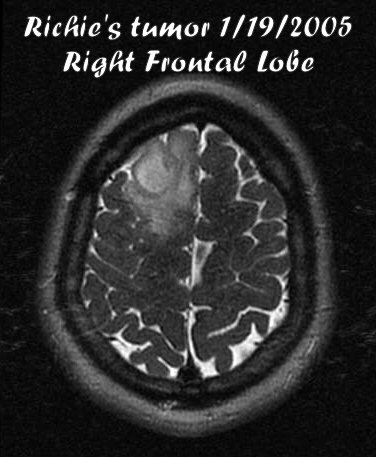

A non-epilectic seizure landed me in St Luke's hospital in Kansas City, MO on January 19, 2005.  After a CT scan and an MRI, the golf ball sized tumor was found in the right frontal lobe of my brain.  Luckily it was not real deep so a craniotomy was planned for that afternoon to remove it.  After 3.5 hours of surgery, the doctor exclaimed that he was happy to have been able to remove all that was visible by the human eye.  This doesn't mean it is all gone, microscopic sized cells and cells in folds of the brain could be left but no way to prove they are there or not.  Hence the reason for radiation and chemotherapy.